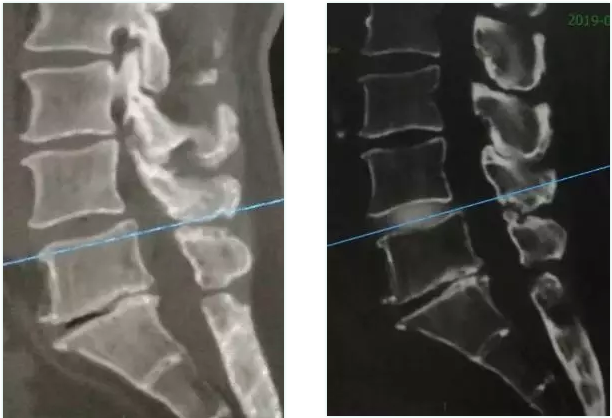

术前磁共振显示腰4/5椎间盘极重度向下脱出游离

术前(左)术后(右)对比显示,游离髓核组织取出干净